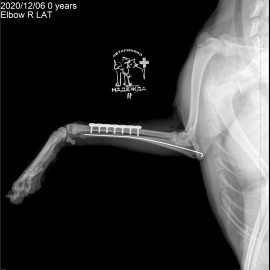

После проведённого осмотра и рентгенологического исследования был поставлен диагноз - перелом правого предплечья. Была проведена операция - остеосинтез правого предплечья.

Снимок 2 после операции.